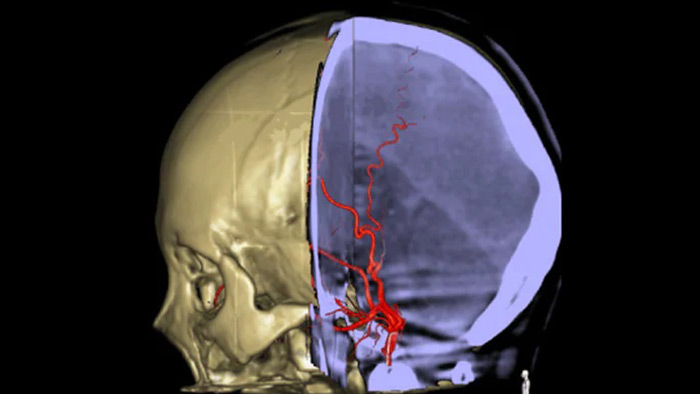

SmartCT Vaso IV

血栓の位置と長さを確認

SmartCT Vasoでは、脳梗塞の梗塞部位の全体像を可視化することができる撮影機能です。SmartCT Vasoは、動脈への造影コーンビームCTに高分解能撮影の技術を組み合わせた撮影技術でrestrictive fillingによる梗塞部位の遠位血管も描出することができ、血栓の位置、長さ、梗塞部位の全体像を視覚化できます。3Dロードマップを組み合わせて使用することにより、術中の血栓回収デバイスのナビゲーションも可能となります。

restrictive fillingによる遠位血管の描出